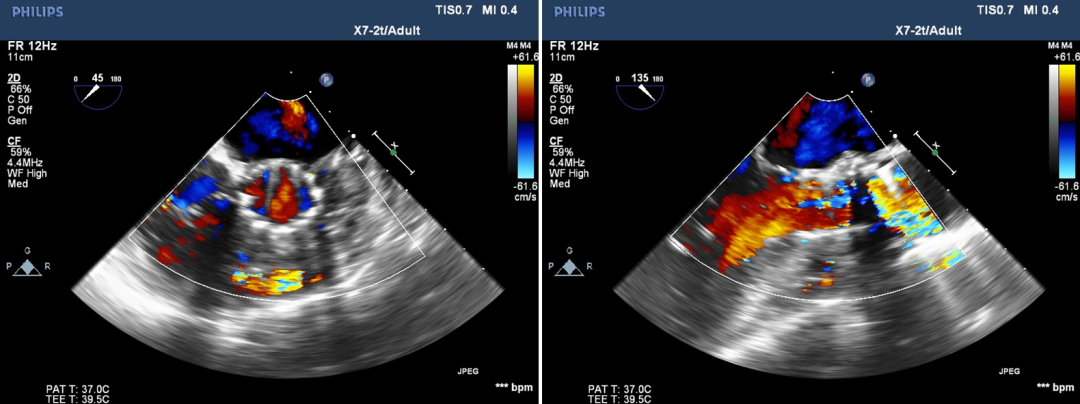

超声影像

瓣膜工作状态良好,极微量瓣周漏

Vmax 1.75m/s,PG 14mmHg

TEE影像,烟囱支架显影清晰,支架内血流通畅